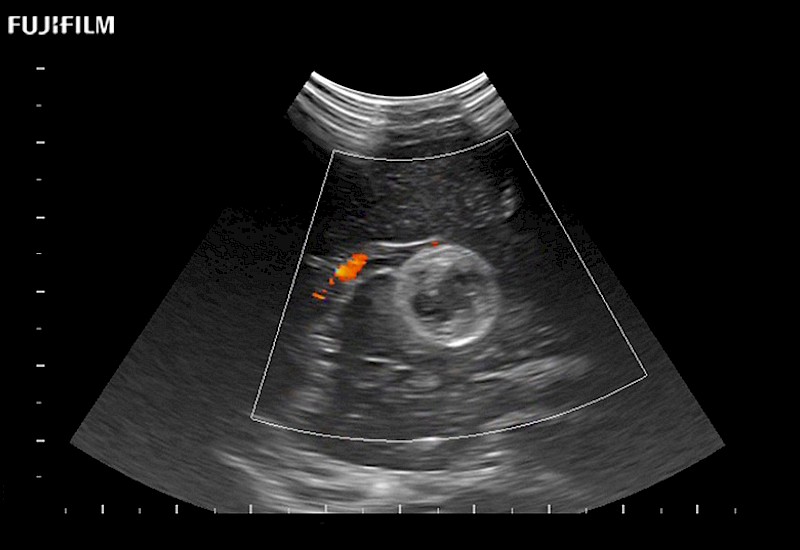

Exclusive 10mm side‐fire linear array transducer with 2.87mm diameter is ideal for real‐time visualization through and behind structures and instant, scalable definition of anatomy and vascularity including the ability to delineate and define tumor margins.

Main Specifications: